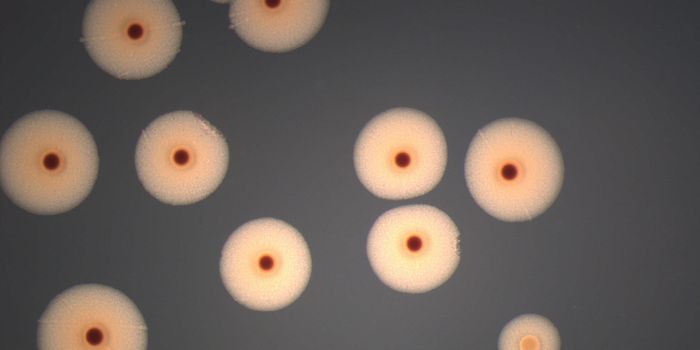

MAR 11, 2025MicrobiologyRevolutionizing Quality Control with ATCC's MicroQuant™ Microbial testing laboratories often face challenges s ...